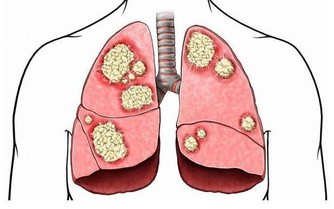

以上就是肝病惡化的十大前兆。患者在明確自己的病情后,治療方面應以適當休息、合理飲食和正確用藥為原則,用藥必須堅持辨證論治,做到準確、合理,切忌所有病人都用一種藥,都開一個方,和保肝藥、營養藥,中西治療藥一起濫用的治法。

此外,疲勞是導致乙肝病情加重的原因之一。肝病最怕累,累了就會加重病情,最好不要過累,覺得承受不了的就不要強去做、平時注意飲食,不酗酒,不要亂吃藥,注意睡眠質量,保持好的心態。發現病情惡化及時治療。下面說一下乙肝患者的飲食。